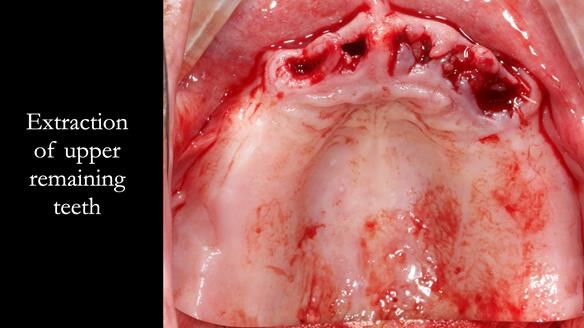

Welcome to Newsletter 62. In this edition, I walk through the process of removing 5 upper anterior teeth, adding to an existing upper RPD, followed by creating and fitting metal based complete dentures for Rafique, a 71 year old man.

The detailed clinical situation and treatment process are outlined below, with clinical work provided by me and technical work by Rowan Garstang. The treatment spanned 12 months, involving removing 5 upper anterior teeth, adding to an existing upper RPD, followed by creating and fitting metal based complete dentures.